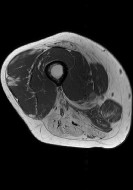

In muscle diseases such as the muscular dystrophies and inflammatory myopathies, there is a significant and urgent need for quantitative, objective biomarkers that can be used to understand disease natural history and perform clinical trials. Advanced, quantitative magnetic resonance imaging methods are sensitive to relevant aspects of disease state; but these methods are typically used only in research contexts, not in clinical radiology clinics. Instead, clinical radiology exams are based on qualitative descriptions of images obtained using conventional imaging methods. This precludes the quantitative comparison of MRI findings to other medically relevant data. As a result, the development of biomarkers that can advance the understanding and treatment of human muscle disease is impaired. However, we have recently obtained promising preliminary results suggesting that image texture analysis methods can be applied to conventionally obtained radiology images and used to predict the degree of muscle wasting and fat infiltration in muscle diseases.

In muscle diseases such as the muscular dystrophies and inflammatory myopathies, there is a significant and urgent need for quantitative, objective biomarkers that can be used to understand disease natural history and perform clinical trials. Advanced, quantitative magnetic resonance imaging methods are sensitive to relevant aspects of disease state; but these methods are typically used only in research contexts, not in clinical radiology clinics. Instead, clinical radiology exams are based on qualitative descriptions of images obtained using conventional imaging methods. This precludes the quantitative comparison of MRI findings to other medically relevant data. As a result, the development of biomarkers that can advance the understanding and treatment of human muscle disease is impaired. However, we have recently obtained promising preliminary results suggesting that image texture analysis methods can be applied to conventionally obtained radiology images and used to predict the degree of muscle wasting and fat infiltration in muscle diseases.

- To develop improved statistical models for predicting the degree of muscle wasting and fat infiltration in muscle diseases from image texture measurements;